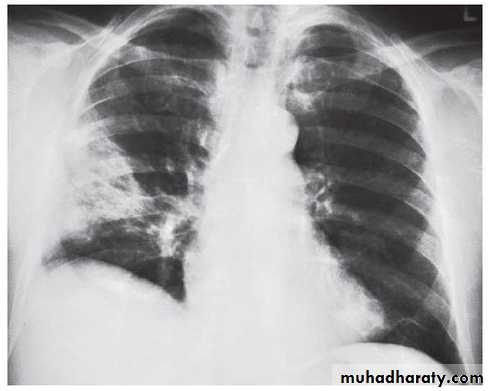

BRONCHOPNEUMONIA

chest practice

Mycoplasma pneumonia. A 35 year old man presents with nonproductive cough and fever